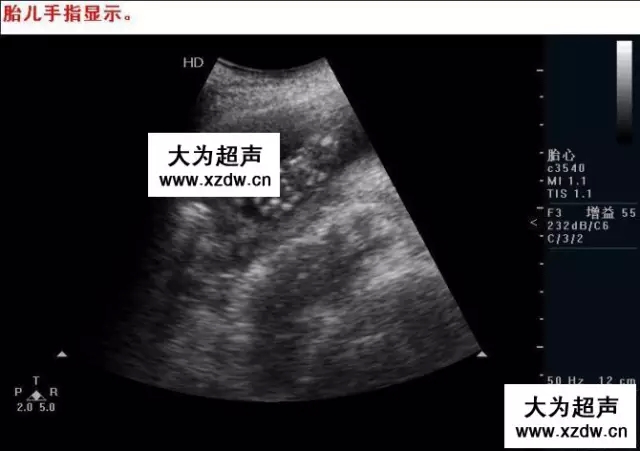

產科超聲正常圖片